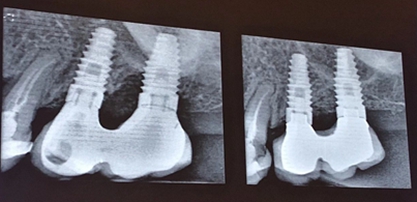

種植體周圍炎是影響牙種植遠(yuǎn)期效果導(dǎo)致種植失敗的主要原因之一。和天然牙一樣,如果口腔衛(wèi)生不良,菌斑滯留,那么細(xì)菌微生物就會(huì)對種植體周圍的軟組織不斷刺激,使機(jī)體產(chǎn)生炎癥反應(yīng),表現(xiàn)為黏膜的紅腫、探診出血甚至溢膿。也可通過X片來評估種植體周圍的骨量情況。

4、種植體周圍炎的治療

手術(shù)方式治療則需通過翻瓣清潔種植體及修復(fù)體上菌斑牙石,推薦在此過程中使用士卓曼鈦刷,因?yàn)樵撯佀⒉粫?huì)損傷種植體表面細(xì)微結(jié)構(gòu)。之后進(jìn)行植骨蓋膜來促進(jìn)種植體周圍吸收部分的骨的重建。